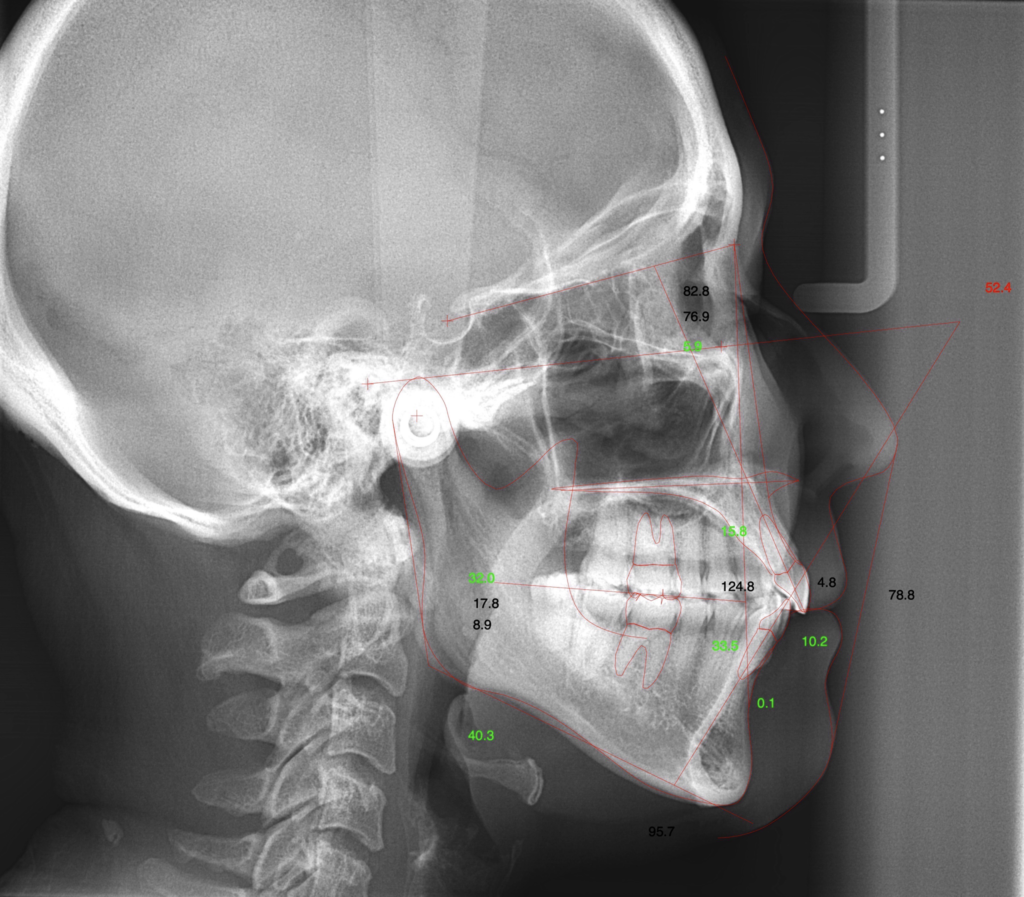

当院では、パノラマというレントゲンだけでなく、CTにて、立体的にどういう骨の形態をしているのか確認した上で慎重に診査診断を行います。

では実際の患者様のレントゲン写真をご覧ください。

この方は、骨格的にも歯並びにも特に目立つ問題がなく、むし歯もできにくかった為、長年歯医者に行かなくても日常生活に支障がでませんでした。

最近、下の前歯の歯茎から膿が出てきた事をきっかけに来院されました。

それでは詳細のレントゲンで骨の状態を確認していきましょう。赤の矢印が骨の位置を示しています。

初診時

歯石取り(歯周初期治療)後

歯周組織再生療法後(外科処置の6ヶ月後)

白く写っているのはワイヤーです。

歯周組織再生療法後に噛み合わせによる負担がかからない様に固定をしています。

この方は全ての処置が完了した後も上手に歯磨きをされ、決められた期間でのメインテナンスにもきちんと来られているので、現在も良い状態をキープされております。

この方は、部分的(垂直的)な骨の吸収だったので、今回の治療が適応でしたが、全体的に骨の吸収がある場合は抜歯になる事もございます。